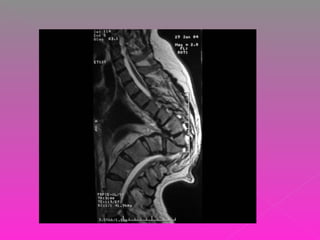

 LA PACIENTE CUENTA CON UNA TAC QUE

REPORTA:

 CUERPO DE T9, CON IMÁGENES

OSTEOLÍTICAS, EXPANSIVAS Y DE PATRÓN

DIFUSO QUE INVADEN CANAL NEURAL EN

UN 50% APROX. ASÍ MISMO HAY LISIS EN

PLATAFORMAS SUPERIOR E INFERIOR Y

PARED ANTERIOR. NO SE OBSERVAN

LESIONES ASOCIADAS.

 DESTRUCCIÓN VERTEBRAL POR PROCESO

TUMORAL SECUNDARIO VS PROCESO

INFECCIOSO.

 INSTRUMENTACIÓN POSTERIOR DE T6-T7 A

T10-T11 MÁS DESCOMPRESIÓN

POSTERIOR, TOMA DE BIOPSIA DE

CUERPOS VERTEBRALES T8, T9.

 CORPECTOMIA T8,T9 Y SUSTITUCIÓN DE

COLUMNA ANTERIOR CON INJERTO ÓSEO

AUTÓLOGO DE CIIZQ.